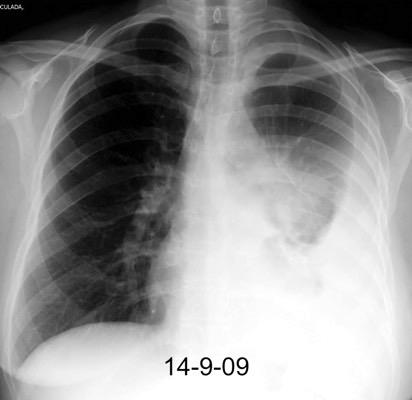

Neumonía a neumococos base izda. con derrame que aumenta.

Broncograma en lateral y en US.

(36-66% en ingresados)